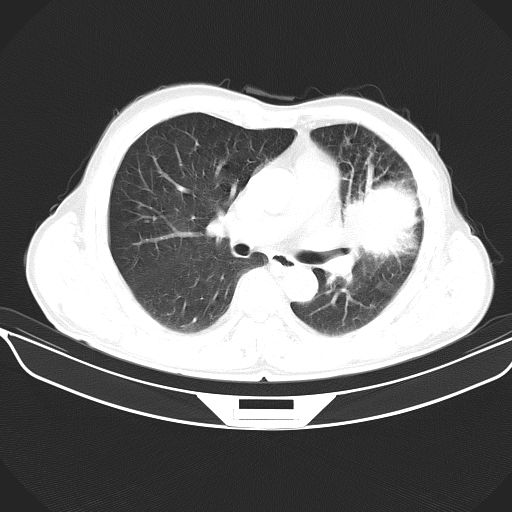

以下是引用心路寻觅在2010-3-1 10:23:00的发言:[br]1、考虑左肺上叶周围型肺癌[br]2、右上肺陈旧性病灶。[br][br][本贴已被 心路寻觅 于 2010-3-1 10:40:18 修改过]

以下是引用shuiyuan在2010-3-1 10:45:00的发言:[br]考虑左肺上叶中心型肺癌伴阻塞型炎症,邻近胸膜受侵。